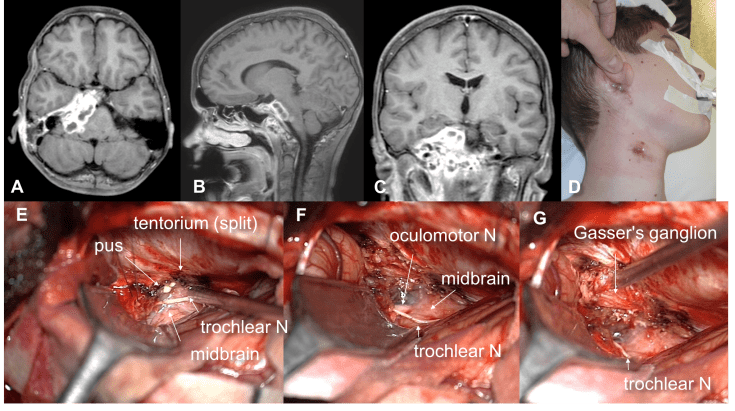

la chirurgie

elle a pour buts :

- d’évacuer les collections purulentes

- d’identifier le ou les germes

- de traiter la porte d’entrée si nécessaire

Elle nécessite souvent d’être répétée, parfois plusieurs fois, car les collections purulentes ont tendance à se cloisonner et récidiver.

d’autre part, la porte d’entrée ORL nécessite souvent d’être obturée dans une second temps. il faut d’emblée anticiper ces réinterventions en réalisant un abord versatile (incision coronale).

la chirurgie est parfois difficile lorsque la collection est localisée à la base du crâne ; il importe alors de ne pas créer de fistule purulente impossible à fermer et donc de choisir un abord endodural (cf. ci-dessous).